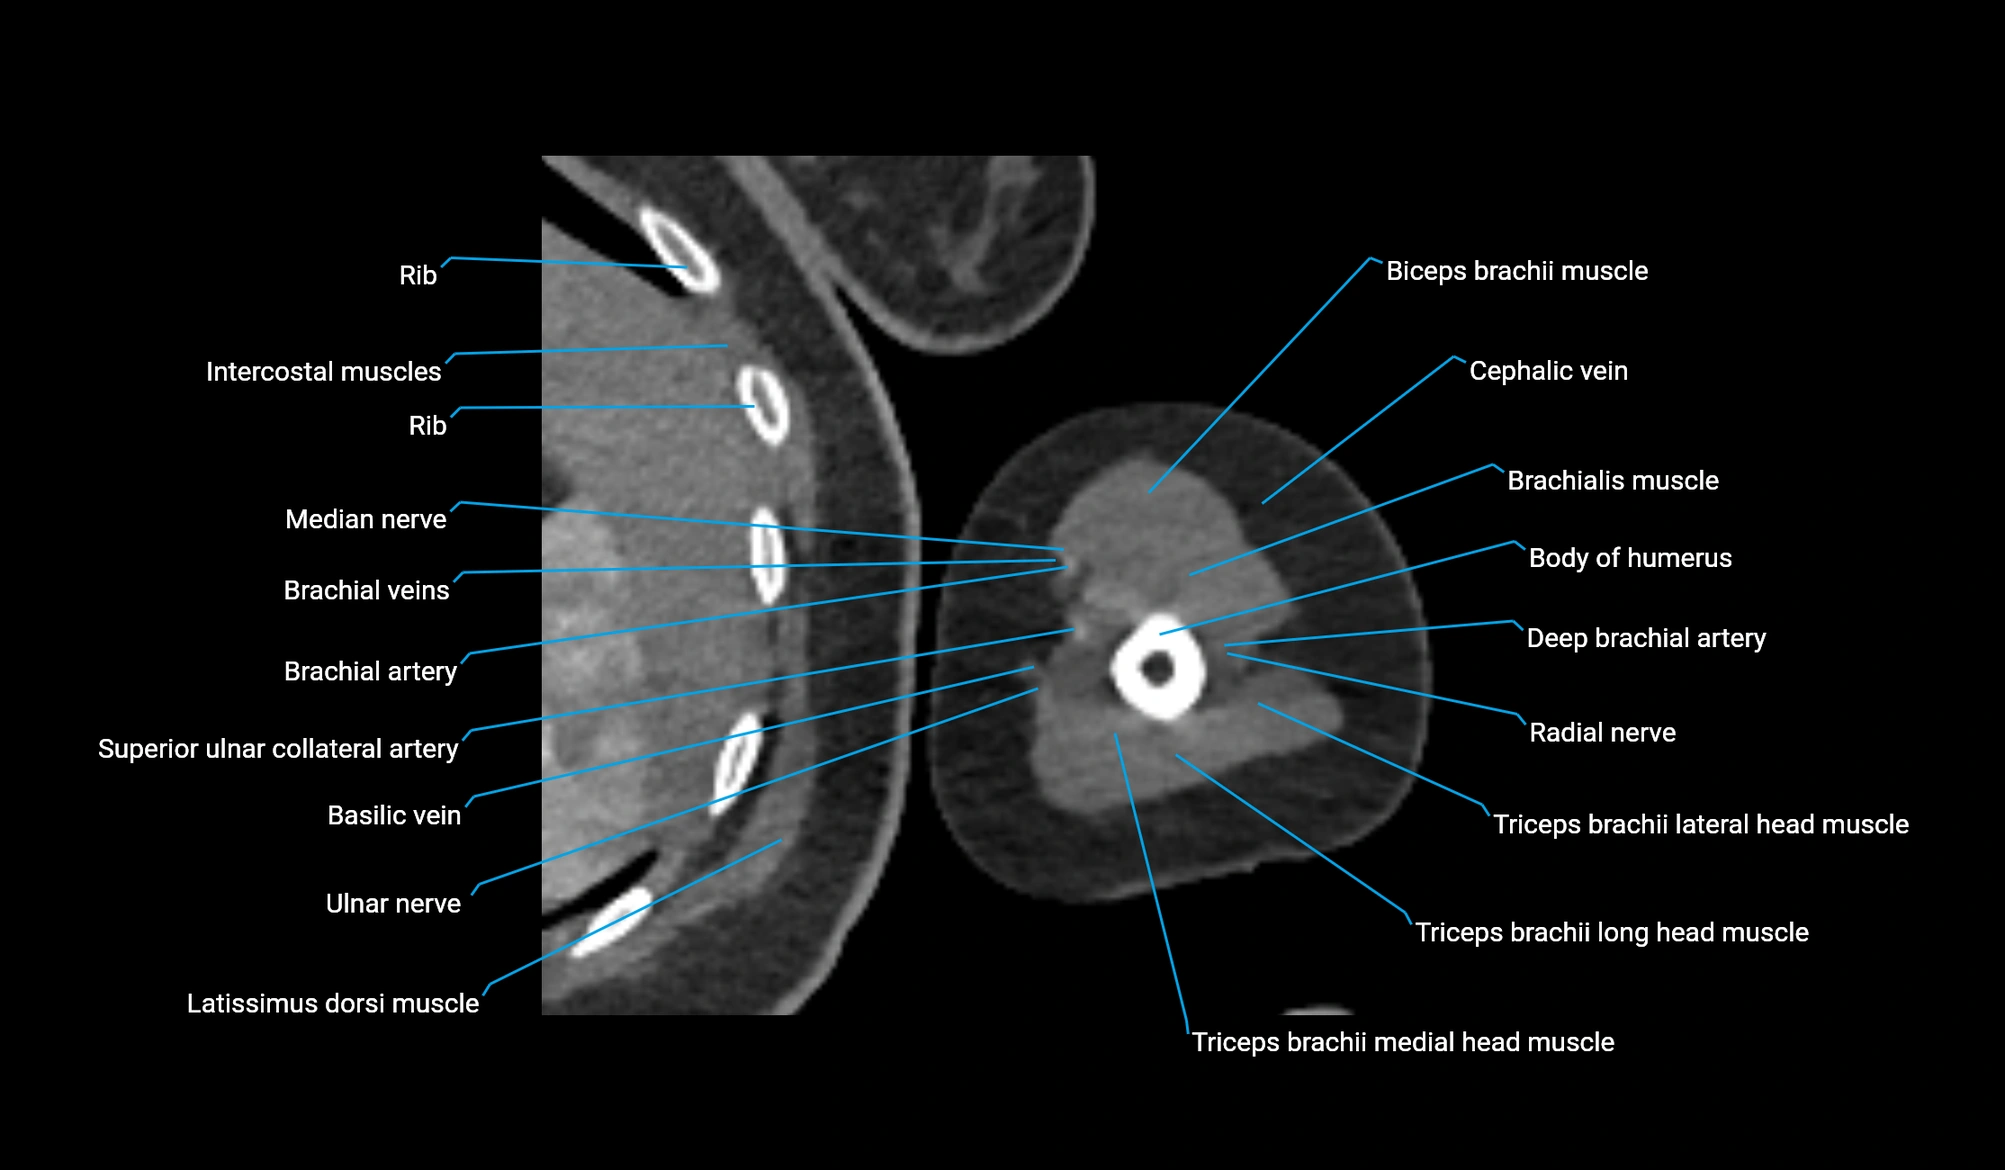

- Body of humerus

- Biceps brachii muscle

- Cephalic vein

- Brachialis muscle

- Deep brachial artery

- Brachial artery

- Superior ulnar collateral artery

- Basilic vein

- Ulnar nerve

- Median nerve

- Long head of triceps brachii muscle

- Lateral head of triceps brachii muscle

- Medial head of triceps brachii muscle